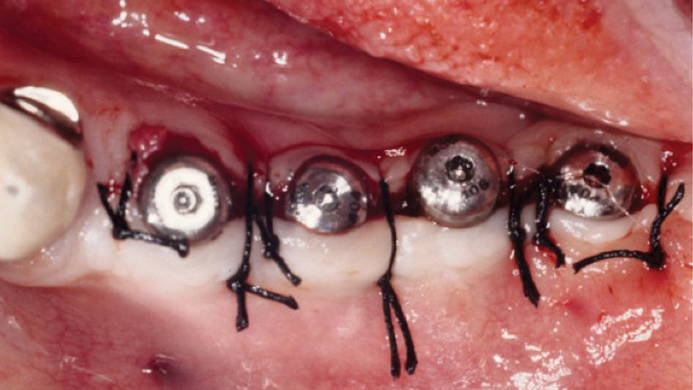

Clinical case: Installation of dental implants in complicated anatomic conditions using crest lifting methods

- Courtesy of Dr.Alexander Lysov, Russia -

AnyRidge, complicated anatomic conditions, crest lift, MICA Kit, Dr. Alexander Lysov, bone regeneration, GBR, #26, maxillary posterior

AnyRidge implant system, MICA Kit